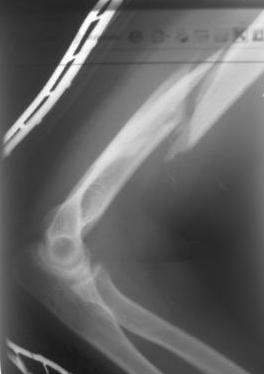

[Ortho] Перелом н\3 плечевой кости. Тактика лечения?

Перелом нестабильный, тактика - если позволяет сосояние больной, оперативное лечение. Как пример см. ниже, можно без скобы - стяжки с ЭПФ. Представленный способ, функциональный, данная больная в качестве внешней иммобиллизации в течение 3-х недель полльзовалась косыночной повязкой, востановление функции плеча полное. Правда травма изолированная, но операция выполнялась через три недели после травмы, тот час после обращения ко мне - иногородняя.